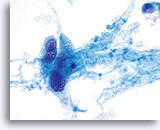

Er kan veelvuldig insnoeren worden waargenomen in zowel endocervicaal adenocarcinoom, als in endometriaal adenocarcinoom.

60x